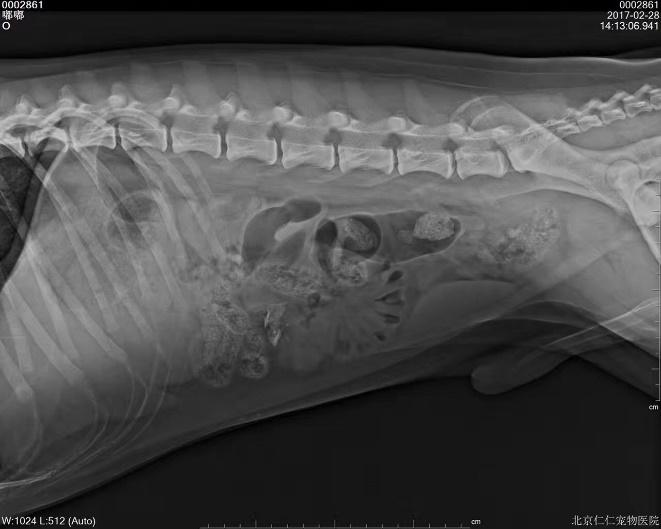

b. X射线检查:对于阻线性较强的物质(如金属、骨头)较容易辨别,对于阻线性与组织密度相似的物体较难确定,但是可以通过消化道灌服造影剂判断是否有阻塞或可包裹物体。

胃的正常大小:胃位于前腹部,隔和胆脏之后。胃排空时位于肋弓以内;从腹底算起,胃的腹侧缘大约在腹腔深度的1/3处。胃充盈时,胃向后向下延伸,与横结肠和腹底部相接。

摆位对

犬猫呕吐的鉴别诊断,犬猫呕吐的诊断和治疗

胃内异物(金毛,手术取出6cm大衣扣子)

c.X线检查。对于阻线性较强的物质(如金属、骨头)较容易辨别,对于阻线性与组织密度相似的物体较难确定,但是可以通过消化道灌服造影剂判断是否有阻塞或可包裹物体。

机械性肠梗阻的读片要点:1.体积增大;2.形态轮廓变化;3.影像密度变化;4.浆膜细节变化。

金毛 线性异物